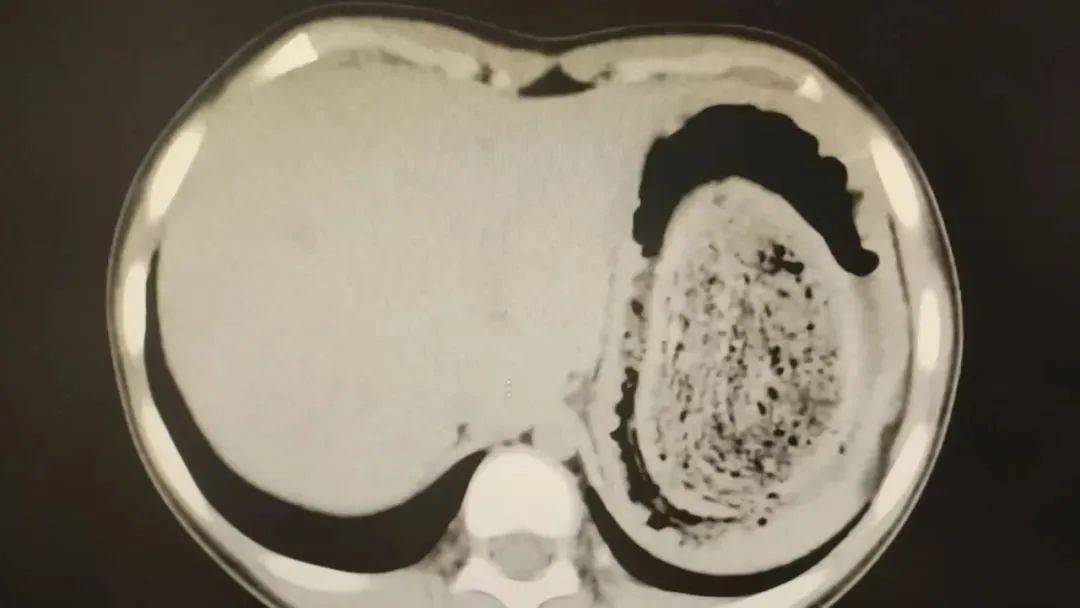

结果出来时,医生都惊呆了:小可的胃里,塞满了成团的头发,几乎占了胃容量的四分之三皇冠登3代理出租。大量不能消化的物质,在胃酸的作用下发生变性,并与食物及其他物质结合形成团块,慢慢变成坚硬的“胃石”。

为了避免用手术方式去除头发团,陈攸涛先让小可喝可乐软化“胃石”,再通过胃镜辅助取出头发,整个过程花了十几个小时,清理出的头发装了两大盆皇冠登3代理出租。

2024年10月,11岁女孩欢欢(化名)因腹痛难耐紧急送到医院,而就在两个月前,欢欢的父母发现她在拔自己的头发,偷偷吃掉皇冠登3代理出租。经检查,医生发现她胃腔和肠管里有大块的毛絮状结石,几乎占据整个胃部。最终,一块长38厘米、宽15厘米、厚10厘米的毛发结石被取出。